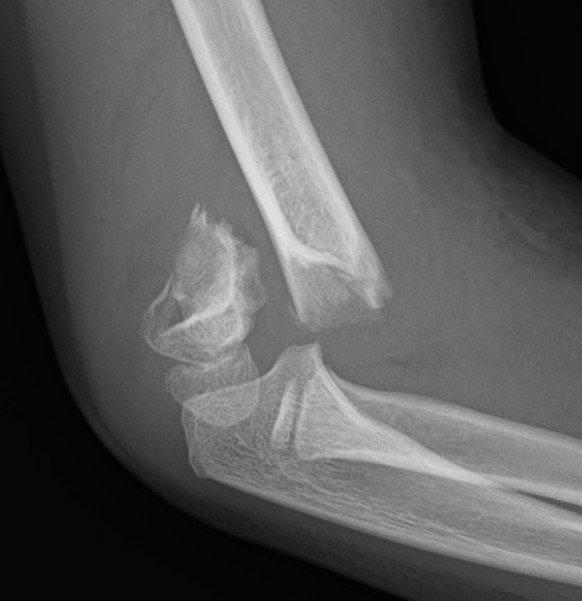

Lateral Xray

Position for good lateral

- thumb vertical

- hand above elbow

Anterior angulation

- shaft - condylar axis

- normally 40o

Lines

Anterior humeral line (AHL)

- should pass through middle of capitellum

Radio-capitellar line

- pass through capitellum

Teardrop

- shadow above the capitellum

- anterior dense line: posterior margin of the coronoid fossa

- posterior dense line: anterior margin of the olecranon fossa

- inferior portion: ossification center of the capitellum